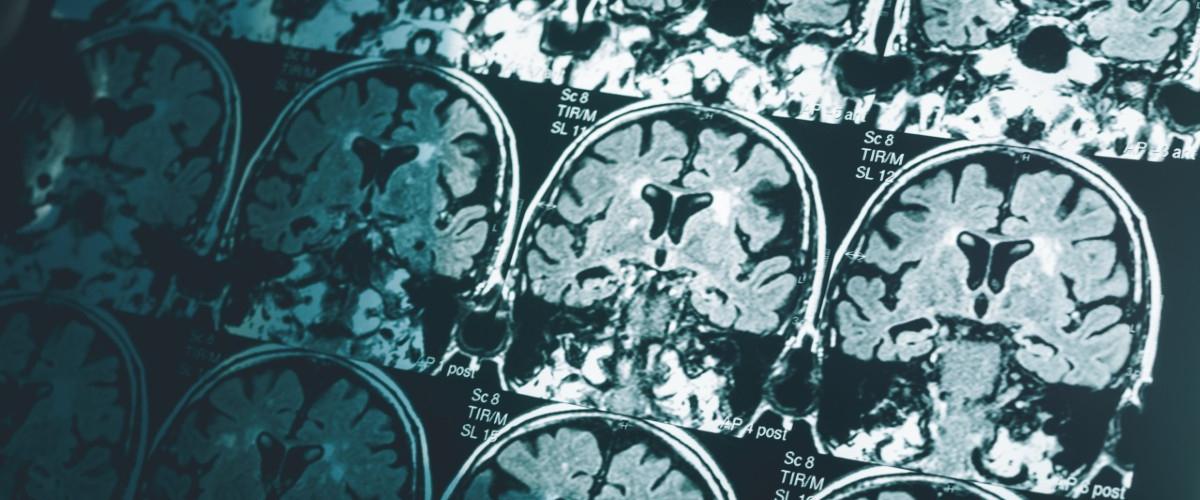

Болезнь Альцгеймера — наиболее распространенная форма деменции — относится к неизлечимым нейродегенеративным заболеваниям, поэтому диагностика на ранней стадии имеет ключевое значение для замедления прогрессирования заболевания. Сегодня определить диагноз достаточно сложно: врачи проводят различные когнитивные тесты, выполняется анализ спинномозговой жидкости, а также проводится сканирование мозга. Сканы необходимы для оценки объема гиппокампа и наличия отложений токсичных белков, однако эта диагностика напрямую зависит от квалификации врача.

Между тем даже очень опытный специалист не может заметить мельчайшие изменения в головном мозге, которые указывают на болезнь. С этой целью ученые из Имперского колледжа Лондона обратились к ИИ — они адаптировали алгоритм, который раннее был разработан для классификации раковых опухолей.

Головной мозг разделили на 115 областей и выделили 660 различных характеристик, по которым затем обучали ИИ.

В 98% случаев ИИ точно определял по МРТ пациента с деменцией. Кроме того, с точностью 79% алгоритм сообщал о стадии нейродегенерации — ранней или прогрессирующей.

Важно подчеркнуть, что тестирование проводилось на пациентах с различными типами деменции, а также среди людей с болезнью Паркинсона и неврологическими заболеваниями. «Сегодня никакие другие простые и доступные методы не могут предсказать болезнь Альцгеймера с таким уровнем точности», — прокомментировал автор работы Эрик Абоагье. Для тестирования ученые использовали данные МРТ-сканирований на стандартном аппарате мощностью 1,5 Тесла.